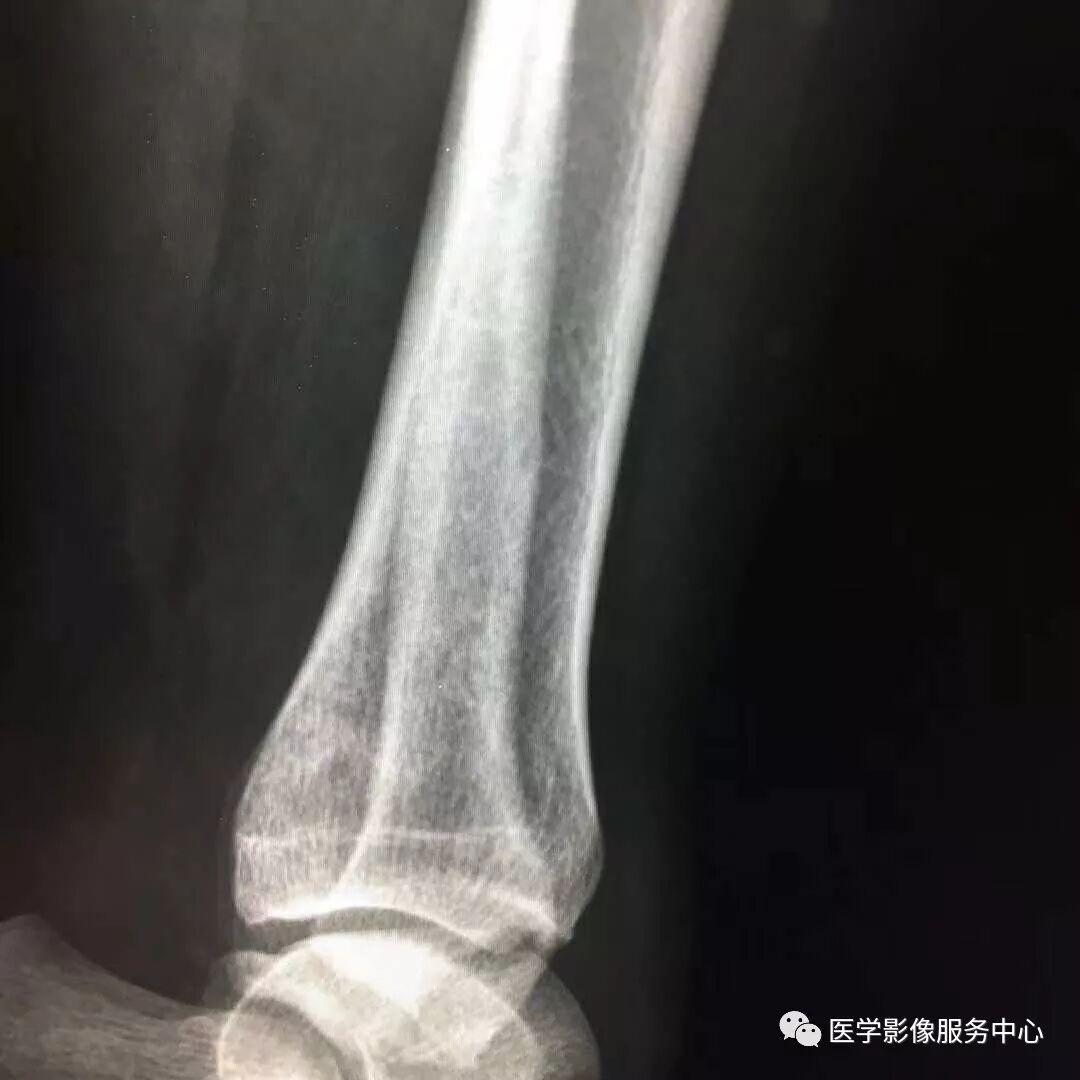

Pilon骨折常常伴随极度粉碎的骨折和严重的软组织损伤,选择合适的手术入路就成了手术的关键。